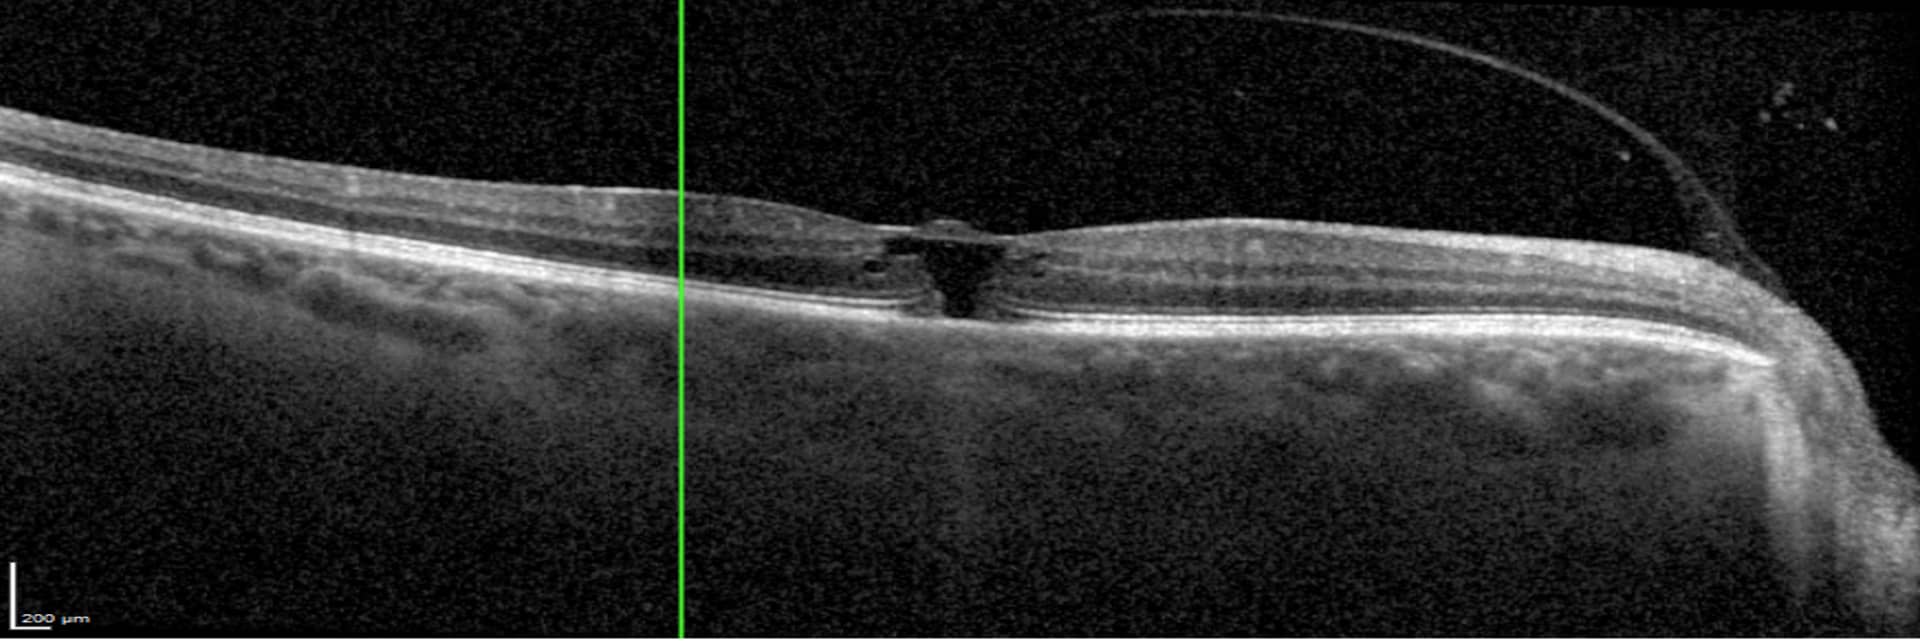

Il s’agit d’une thrombose du système artériel de la rétine neurosensorielle pouvant survenir à différentes localisations (Artère centrale [57%], branche de l’artère centrale [38%], artère cillio-rétinienne [5%])

– Baisse d’acuité visuelle brutale unilatérale plus ou moins profonde

– Amputation brutale d’une partie du champ visuel

– Pas de douleur ni rougeur oculaire

Une occlusion artérielle rétinienne est une urgence médicale ! C’est un AVC avant preuve du contraire et ceci doit être exclu en priorité de l’atteinte sur l’œil. En effet, c’est parfois le seul signe d’une maladie systémique potentiellement létale.

Un bilan systémique et cardiovasculaire doit en ce sens être réalisé en urgence pendant une courte hospitalisation !

Une angiographie rétinienne est également souvent réalisée par votre ophtalmologue, afin de vérifier l’état de perfusion rétinienne au décours.

Le traitement est organisé conjointement avec les équipes de neurologie, cardiologie et radiologie interventionnelle dans le cas d’une indication éventuelle à une thrombolyse systémique.

Un suivi ophtalmologique et systémique au long cours est ensuite requis.

Toute baisse d’acuité visuelle brutale unilatérale doit être investiguée rapidement, si possible dans les 6h suivant le début des symptômes, par un ophtalmologue.

Dans cette pathologie chaque minute compte !